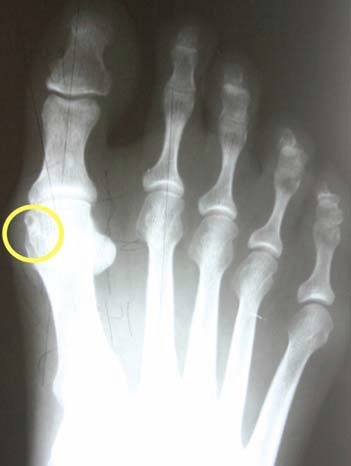

Mild Bunion Xray

Mild bunion xray. Surgery to place cartiva synthetic cartilage implants in the large joints of my big toes has reduced pain and restored motion and function. As in weightbearing cast weightbearing x rays etc. It is weight bear but bear weight is better grammar.